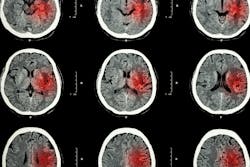

These cells are called NKG2D+CD8+ T cells and researchers say their aggressive response is responsible for neurological damage suffered from infections beyond just Zika, like COVID-19 and even septic shock.

The aggressive response is the result of the body producing large amounts of inflammatory proteins called cytokines, which in moderation help to coordinate the body’s response in battling an infection or injury by telling immune cells where to go and what to do when they arrive.

"If our body’s immune cells overreact and over produce inflammatory cytokines, this condition will lead to non-specific activation of our immune cells which in turn leads to collateral damage. This can have severe consequences if it happens in the brain,” Ashkar says.